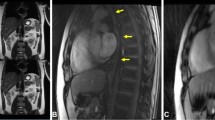

Twelve consecutive patients who presented themselves in our surgical outpatient clinic were included in this study. Gastroesophageal reflux could be identified in 11 out of 12 patients using real-time MRI. Regurgitation during the Valsalva maneuver could be well visualized in all 11 cases. Figure 3A presents a typical example, where the swallowed pineapple juice (high-intensity signal) returned from the stomach to the oesophagus through the sphincter. The image (single frame) was selected from the corresponding real-time MRI recording shown in Supplementary Movie S11.

Real-time MRI of gastroesophageal swallowing in patients with (A) reflux, (B) hiatal hernia, (C) achalasia, (D) telescoping oesophagus after fundoplication, (E) thoracic stomach and (F) functional heartburn without reflux evidence. Individual images (50 ms acquisition time, 2 × 2 mm2 resolution, 8 mm section thickness) were selected from corresponding movies (S11 to S17 in Supplementary Appendix). Arrows indicate (A,B) bolus regurgitation from the stomach into the oesophagus during Valsalva maneuver and (C–F) bolus transport from oesophagus into the stomach (C–F).

In addition to gastroesophageal reflux, three gastric hernias, one achalasia, one telescoping stomach after fundoplication and one thoracic stomach were identified among the 11 affected patients. For all patients with hernias, the hiatal oesophagus led to a functional inhibition of the bolus outflow from the hernial part of the stomach, which was cranial of the diaphragm, to the lower part of the stomach below the diaphragm. An example is shown in Fig. 3B and Supplementary Movie S12, where the hiatal hernia is formed only during the Valsalva maneuver, but was not present during swallowing (Supplementary Movie S13). For the patient with achalasia, a wide oesophagus (7.0 cm) was identified with almost no visible peristaltic movement during swallowing. The transport of the bolus was limited to a very narrow passage through the sphincter (Fig. 3C and Supplementary Movie S14). In this patient clinical manometry was technically not possible. The patient with telescoping stomach had undergone fundoplication two years earlier with absence of symptoms for the initial 6 months. Real-time MRI revealed a filiform stenosis, located 2.8 cm distal to the sphincter at the side of fundoplication. It led to inhibition of the gastric clearance between the sphincter and the fundoplication (Fig. 3D and Supplementary Movie S15). Figure 3E and Supplementary Movie S16 show a patient with complete dislocation of the stomach in the thorax and a deviation of the oesophagogastric junction.

It should be noted that all 11 patients with visible oesophageal regurgitation during Valsalva maneuver had DeMeester scores >14.7, indicating gastroesophageal reflux. One patient with no visible reflux or associated pathological findings in real-time MRI had a low DeMeester score (Table S2 in Supplementary Appendix) and also no gastroscopic evidence for reflux (Fig. 3F and Supplementary Movie S17).